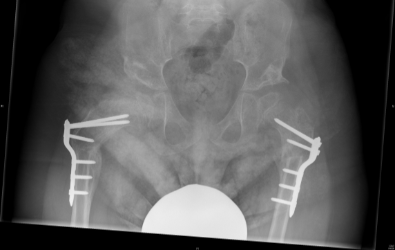

Children with cerebral palsy which are non-walkers need to be screened for hip dislocation. Hip dislocation is common in children with cerebral palsy that are restricted in wheelchairs.  Prevention of hip dislocation is important because it causes severe pain, lower limb deformities and scoliosis. In many countries universal pre-symptomatic hip screening is performed which has resulted in significant reduction in the number of hip dislocations. It is therefore recommended that regular clinical and radiological assessment is performed in children with cerebral palsy that are not able to walk.  In order to avoid hip dislocation the doctor depending on clinical and radiological assessment in each patient can recommend physiotherapy or orthotic treatment, Botox injections or surgical intervention in order to release soft tissues. However, when hip dislocation results in femoral head uncovering of more than 40%, surgical intervention is required in order to reduce the hip, usually with a femoral and/or a pelvic osteotomy.

The x-rays below are of a child with cerebral palsy (a non-walker) with bilateral hip dislocation and severe pain. The patient underwent bilateral femoral and pelvic osteotomies in order to reduce the hips.

Post-operative